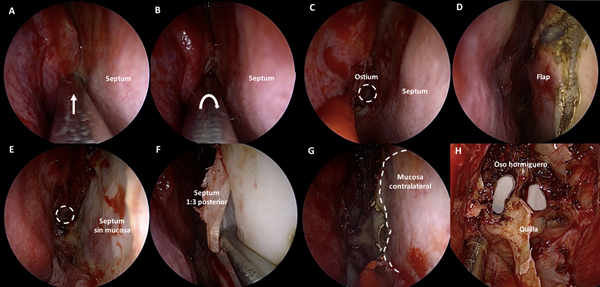

Se procede a la luxación hacia medial y desplazamiento hacia lateral de ambos cornetes inferiores. Luego, se coloca cotonoide embebido en vasoconstrictor entre el cornete medio y el septum nasal a cada lado. Acto seguido, con un disector de Cottle, se desplaza con delicadeza cada cornete medio hacia lateral. El cornete medio no debe ser resecado ni fracturado. Esta maniobra genera un corredor quirúrgico que permite el acceso al receso esfeno-etmoidal a cada lado (Figura 1 A-H).

Figura 1. Fase nasal: tratamiento de los cornetes. A-D: fosa nasal derecha. A-B: lateralización de cornete inferior derecho. C-D: lateralización de cornete medio derecho. E-H: fosa nasal izquierda. E-F: lateralización de cornete inferior izquierdo. C-D: lateralización de cornete medio izquierdo.